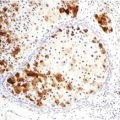

Fig. 72.3

Cutaneous metastases from colon adenocarcinoma (Sister Mary Joseph’s nodule). Infiltrating atypical glandular structures